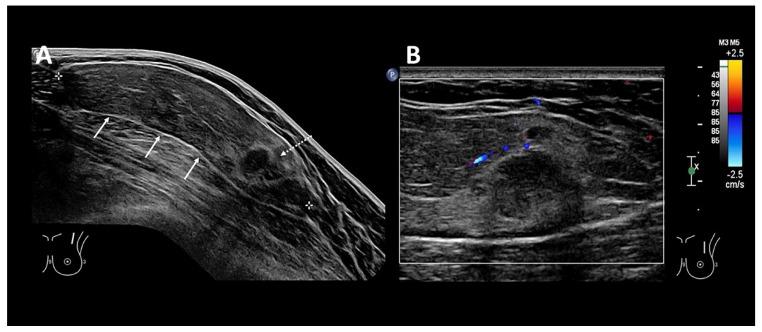

A 50-year-old woman with no past medical history presented with a left anterior chest wall mass that was clinically soft, mobile, and non-tender. A targeted ultrasound (US) showed findings suggestive of a lipoma. However, focal "mass-like" nodules seen within the inferior portion suggested malignant transformation of a lipomatous lesion called for cross sectional imaging, such as MRI or invasive biopsy or excision for histological confirmation. A T1-weighted image demonstrated a large lipoma that has a central fat-containing region surrounded by an irregular hypointense rim in the inferior portion, confirming the benignity of the lipoma. An ultrasound-guided photoacoustic imaging (PA) of the excised specimen to derive the biochemical distribution demonstrated the "mass-like" hypoechoic regions on US as fat-containing, suggestive of benignity of lesion, rather than fat-replacing suggestive of malignancy. The case showed the potential of PA as an adjunct to US in improving the diagnostic confidence in lesion characterization.

一名无既往病史的50岁女性因左前胸壁肿物就诊,该肿物在临床上质地柔软、可活动且无压痛。靶向超声(US)检查结果提示为脂肪瘤。然而,在肿物下部可见局灶性“肿块样”结节,提示脂肪瘤发生恶变,因此需要进行断层成像,如MRI,或进行侵入性活检或切除以进行组织学确诊。T1加权图像显示一个大脂肪瘤,其下部中央有一个含脂肪区域,周围有不规则低信号边缘,证实了脂肪瘤的良性性质。对切除标本进行超声引导下光声成像(PA)以获取生化分布,结果显示超声上的“肿块样”低回声区域为含脂肪区域,提示病变为良性,而非提示恶性的脂肪替代区域。该病例显示了PA作为US辅助手段在提高病变特征诊断信心方面的潜力。